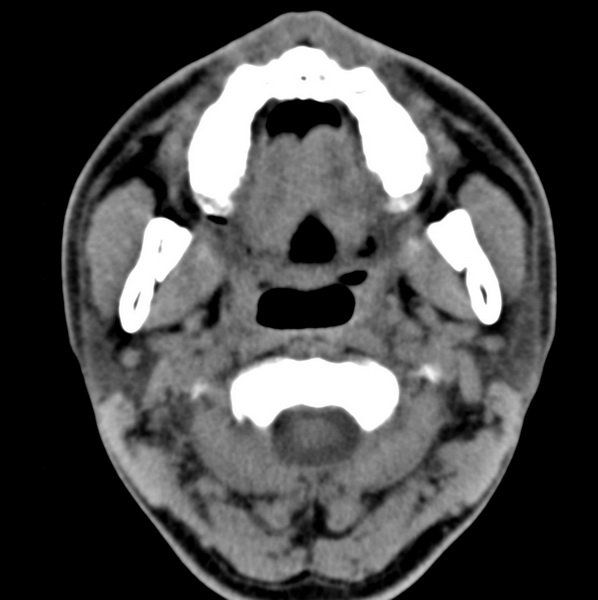

男、31、鼻咽部肿瘤放疗后请帮忙看看。

效果好,右侧破裂孔扩大,局部骨质缺损,为颅底骨质破坏。

1)鼻咽部肿瘤侵犯颅底放疗术后改变。2)左侧蝶窦炎。

咽后壁增厚,左侧咽鼓管隆突增大、咽鼓管咽口变浅,同侧咽旁间隙较窄。右侧颅底骨质破坏?为什么不在同一侧?

鼻咽部肿瘤侵犯颅底放疗术后改变.